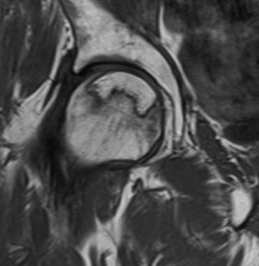

Gradient echo

Accelerated T2 sequence

- very good for ligaments and articular cartilage

Images are fast but very susceptible to chemical shifts which can produce artefacts

Shows cancellous bone as black which can be helpful